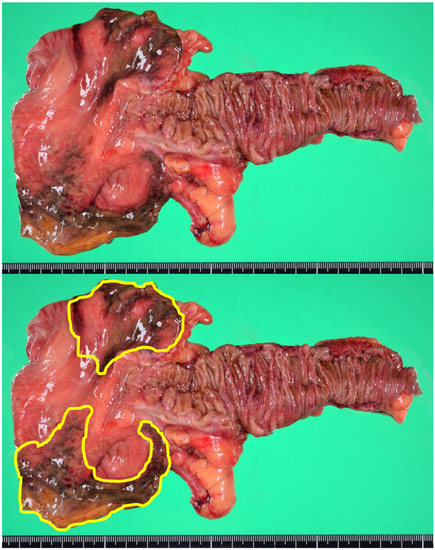

About 10 h after symptoms onset, we performed a laparoscopic-assisted ileocecal resection. After the resection of the damaged intestine, extracorporeal end to end anastomosis was performed. The specimen revealed localized ischemic change on the anti-mesenteric side of the cecum (Figure 3). Microscopically, the transluminal ischemic change was confirmed.

Figure 3.

The specimen showed localized ischemic change on the anti-mesenteric side of the cecum. The enclosed area in the lower picture showing the damaged wall.